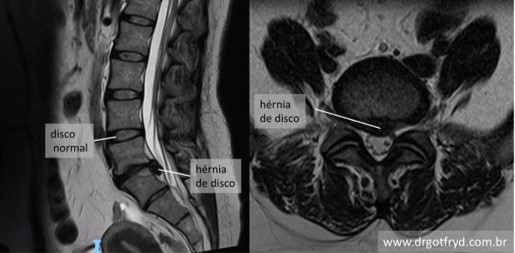

Para a gente entender direitinho, vamos imaginar a nossa coluna como uma pilha de tijolos (as vértebras) com “almofadinhas” entre eles (os discos intervertebrais). Essas almofadinhas são essenciais, agindo como amortecedores, dando flexibilidade e protegendo a coluna.

A hérnia acontece quando uma dessas almofadinhas, por algum motivo – seja por sobrecarga, má postura ou até um movimento brusco –, se desgasta ou se rompe. Aí, parte do seu conteúdo gelatinoso extravasa, e, adivinhe, pode apertar um nervo que está passando ali perto. É essa compressão que causa aquela dor que a gente tanto teme, muitas vezes irradiando para outras partes do corpo.

Os sintomas variam bastante, dependendo de onde a hérnia está localizada. Se for na região lombar, você sente aquela dor chata nas costas que pode descer pela perna, com formigamento ou até fraqueza no pé, um verdadeiro tratamento para dor lombar vira prioridade. Já na cervical, a dor pode ir para o braço, ombro e pescoço, acompanhada de dormência ou perda de força na mão.